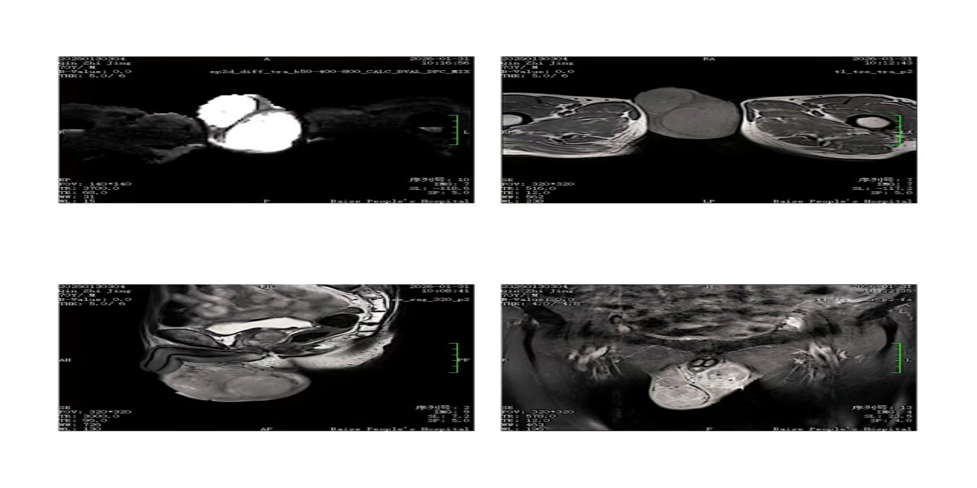

| 影像学检查:(点击查看大图) | 下腹部MRI:双侧睾丸肿大 |

| 患者详情: | 主诉:因双下肢疼痛5月余,发现胫腓骨骨质破坏9天入院。 现病史:患者自诉5月前无明显诱因下出现双下肢疼痛,为阵发性隐痛,持续时间为数分钟至1小时,疼痛科自行缓解,近日自觉疼痛症状加重,于2026-01-19到巴马县人民医院就诊,完善双下肢DR提示双侧胫腓骨骨质破坏,现进一步诊治来我院就诊,完善双下肢DR提示双侧胫腓骨骨质破坏,拟”骨继发恶性肿瘤“入院。 专科情况:双侧胫腓骨压痛及触动;双侧睾丸增大,左侧睾丸肿物约7CM×5CM,右侧睾丸肿物约4CM×4CM。 实验室检查:血常规、肝肾功能、电解质未见异常。 为进一步明确肿物病变性质,常规局部麻醉后用一次性18G全自动活检针在超声引导下穿刺双侧睾丸病灶,引出四条索状组织送病检。 |